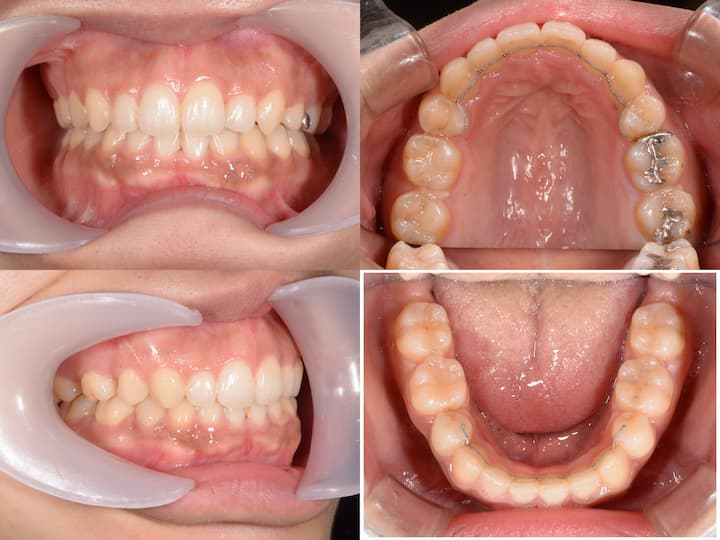

口元の突出感のハーフリンガル矯正

Before

After

治療期間: 1年5ヶ月

上下顎4番を抜歯して、アンカースクリューで大臼歯を固定し、前歯を後方に移動しました。

初診時年齢24歳10ヶ月の患者様です。

口の閉じ辛さと歯の重なりを主訴にご来院されました。

上下左右4番を抜歯してアンカースクリューで上顎6番を固定して前歯を後方に牽引しました。

さらに下顎骨が後方位だったため、上顎大臼歯を圧下(上方向に移動)して下顎骨の前上方への回転を促しました。

本症例は治療期間が1年5ヶ月と比較的短く、前歯の移動量が大きいことから後戻りリスクが高くなります。

フィックス型リテーナーで前歯を固定して、その上から1.0mmのマウスピースで後戻りを防止しています。